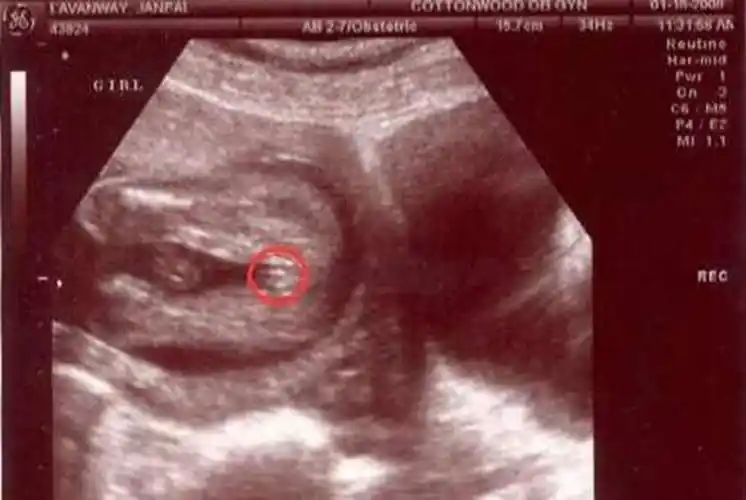

妇产科医生:别纠结指标了,没啥关系_男孩女孩_检查_女性